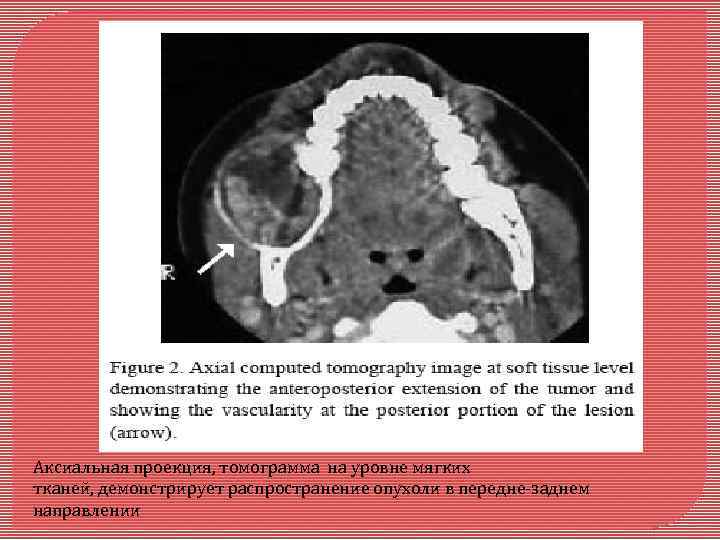

Кальцифицирующая эпителиальная, одонтогенная опухоль Является редкой доброкачественной одонтогенной опухолью, которая составляет приблизительно 1 % всех одонтогенных опухолей. Её происхождение спорно. Кальцифицирующая эпителиальная, одонтогенная опухоль случай запущенной КЭОО, связанной с ретинированным правым вторым моляром в нижней челюсти молодой темнокожей пациентки

Панорамный рентгеновский снимок, показывающий большим и хорошо , отграниченное повреждение, вовлекающее нижней челюсти, от второго коренного зуба к первому премоляру. ___

Аксиальная проекция, томограмма на уровне мягких тканей, демонстрирует распространение опухоли в передне-заднем направлении